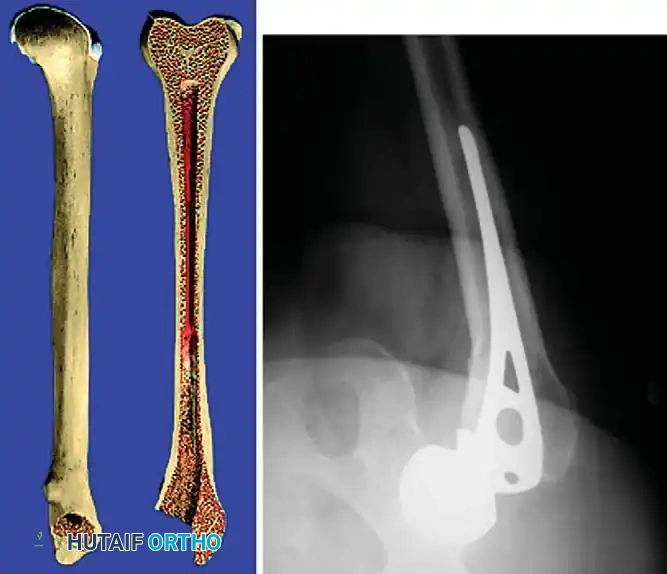

Femoral Reconstruction

Femoral bone loss dictates stem selection. The fundamental biomechanical principle of femoral revision is to achieve rigid fixation in healthy, diaphyseal bone, bypassing the proximal deficiency by a minimum of two cortical diameters (typically 4-6 cm).

Implant Options:

1. Fully Porous-Coated Cylindrical Stems: Excellent long-term survivorship in Type I and II femoral defects. They rely on extensive diaphyseal scratch fit.

2. Modular Fluted Tapered Stems: The modern workhorse for severe (Type III and IV) defects. The flutes provide rotational stability, while the 2-to-3 degree taper achieves axial stability via three-point fixation in the diaphysis. Modularity allows independent adjustment of version, offset, and leg length after the distal stem is rigidly seated.

Pitfall: When seating a diaphyseal-engaging stem, prophylactic cerclage cabling of the distal femur is highly recommended to prevent catastrophic intraoperative splitting of the diaphysis during final impaction.